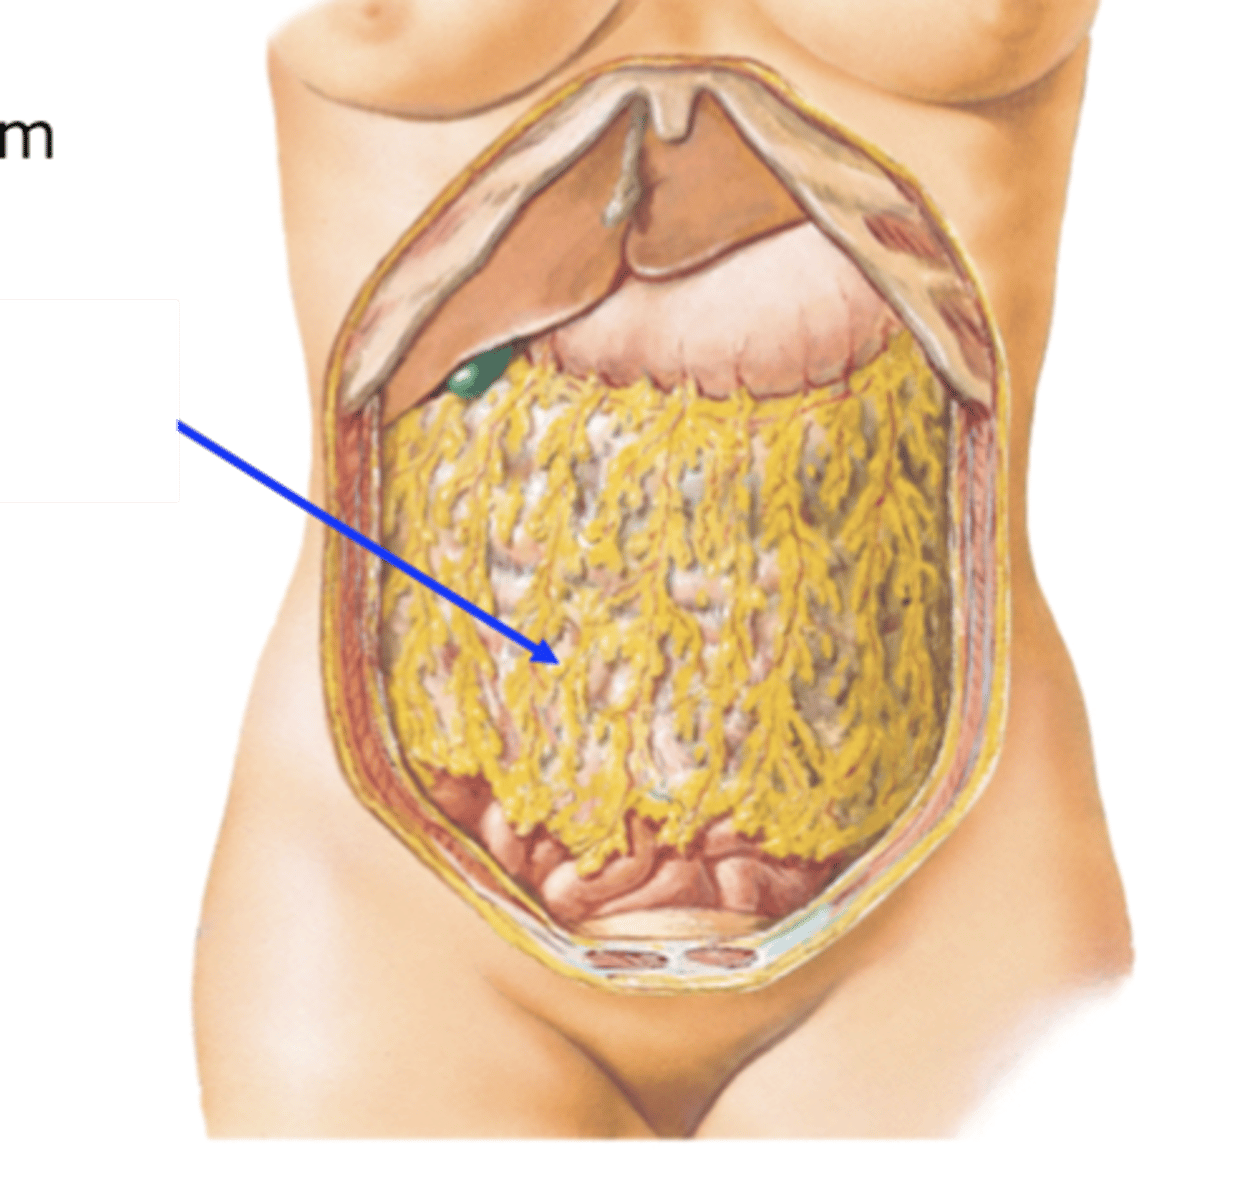

greater omentum

transverse mesocolon

mesentery proper

mesoappendix

sigmoid mesocolon